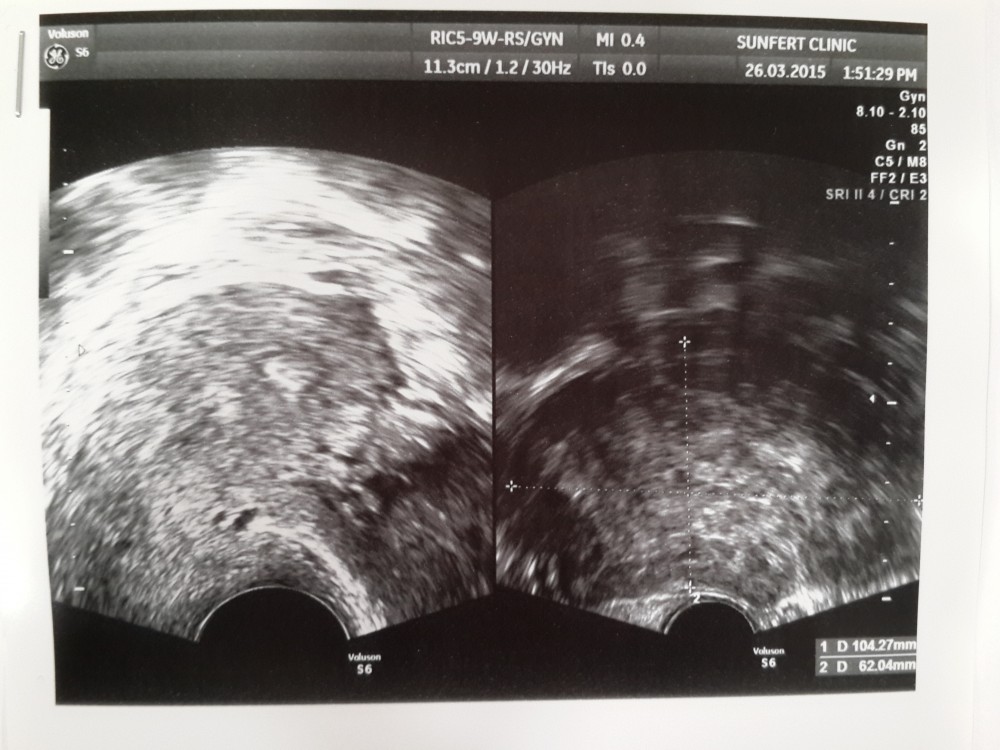

When I was ready, Dr Wong came over to give me an ultrasound.

I was sure I am fine. I am a young lady with no health issues. But to my surprise:

“That is very big! You have a growth,” exclaimed Dr Wong. Then he paused. “No, nothing to worry about. It is nothing cancerous. It is just a growth.”

“It’s just a muscle growth.”

Then he asked me to relax. And gave me a scan at ‘you know where’. It’s pretty uncomfortable. The only comforting words after the discovery of the growth is:

“Good! Good! I can see you eggs. Very nice.”

After the scan, the nurse ushered me back to the consultation room. Dr Wong started explaining to us about the uterus, the eggs and so on. And then, what both of us wanted to know: The Growth.

It is called a fibroid. It is a 10cm fibroid which is very big, bigger than my uterus. The good news is that I can simply remove it with a surgery which Dr Wong is specialize in.

And the better news is that we are so glad that we didn’t try for a baby before the check up. The fibroid is way too big. It would endanger the baby. Not only that, it is below my uterus meaning I can’t give birth naturally. And even with cesarean, it will be very complicated.